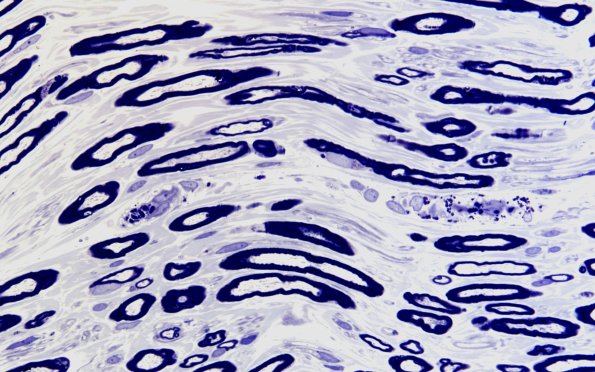

Washington University Experience | PERIPHERAL NEUROPATHY | 18 HEREDITARY DISORDERS | Fabry Disease | 1A5 Fabry Dz (Case 1) 60X 2

This longitudinal section shows inclusions in a large endoneurial vessel but not in Schwann cells. (plastic sections)